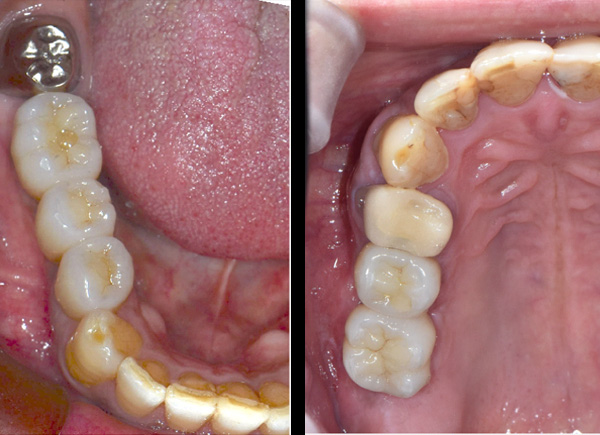

BEFORE

AFTER

| 年代・性別 | 50代 男性 |

|---|---|

| 主訴 | 右下の歯がないのでインプラントをして欲しい |

| 治療期間 | 約6ヶ月 |

| 費用 | 600,000円 |

| 治療内容 | インプラント、骨造成、結合組織移植、セラミック修復 |

| 治療に伴うリスク | インプラント周囲炎 セラミックの破折、脱離 |